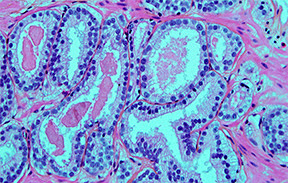

| Imagerie par microscopie optique d'un cancer de la prostate. Copyright J.L. KEMENY / SCIENCE PHOTO LIBRARY |

Les scores de Gleason sont appliqués par les

pathologistes sur la base de la morphologie du cancer de la prostate pour

décrire la perte de structure du tissu; ils sont fortement corrélés avec l’agressivité

de la maladie et le devenir des patients.